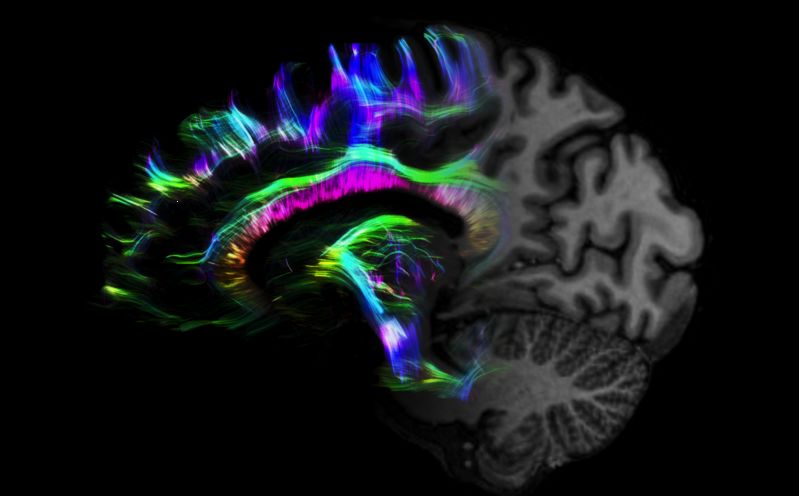

MAGNETOM Terra在業(yè)界首次實(shí)現(xiàn)了兩倍于傳統(tǒng)7T的超強(qiáng)梯度性能,實(shí)現(xiàn)超快速、超高效、超高分辨功能磁共振成像。如此高性能的梯度系統(tǒng)無論對(duì)于科研還是臨床都帶來了更多可能。

1毫米的各向同性分辨率DTI:神經(jīng)纖維束的交叉細(xì)節(jié)顯示